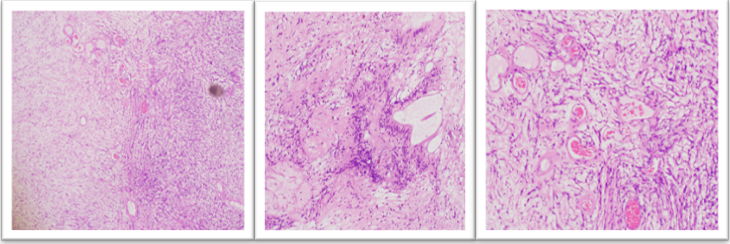

Histopathological evaluation of the submandibular gland revealed features of chronic sialadenitis with ductal dilatation and stromal fibrosis. Examination of the neck mass showed a well-circumscribed spindle cell neoplasm with alternating hypercellular Antoni A areas and hypocellular Antoni B areas. Verocay bodies were also identified. Additionally focal clusters of blood vessels with hyalinized walls were noted (Figure 3).

Figures 3 (Left–Middle–Right, H&E): Left (4×): Schwannoma showing alternating Antoni A(hypercellular) and Antoni B (hypocellular/myxoid) areas. Middle (10×): Verocay bodies with nuclear palisading in parallel rows separated by acellular eosinophilic (basement membrane–like) material. Right (4×): Focal clusters of thick-walled vessels with prominent perivascular hyalinization.

On immunohistochemistry the lesional cells showed diffuse positivity for S100 and SOX-10, supporting Schwann cell lineage while CD38 and CD163 were negative. The overall histomorphology and immunohistochemistry profile were diagnostic of schwannoma (Figure 4).

Figures 4: (Composite immunohistochemistry, 4×; clockwise from upper left ): CD38 shows no immunoreactivity in tumor cells (negative), CD163 highlights no lesional histiocytic population (negative), S100 shows diffuse strong positivity and SOX10 demonstrated strong nuclear positivity in tumor cells confirming Schwann cell differentiation in keeping with schwannoma.